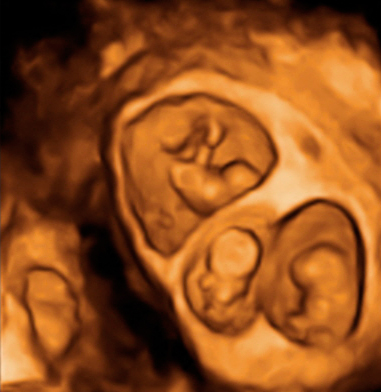

Ecografía semana 12: Gemelos en bolsas independientes

La membrana es muy gruesa

Imagen de un embarazo gemelar que recoge tres ecografías 2D y una en 3D. Los cuatro ultrasonidos demuestran que los bebés están alojados en bolsas independientes con placentas también independientes. Y la membrana que separa los fetos es muy gruesa, según se aprecia en la imagen tridimensional.